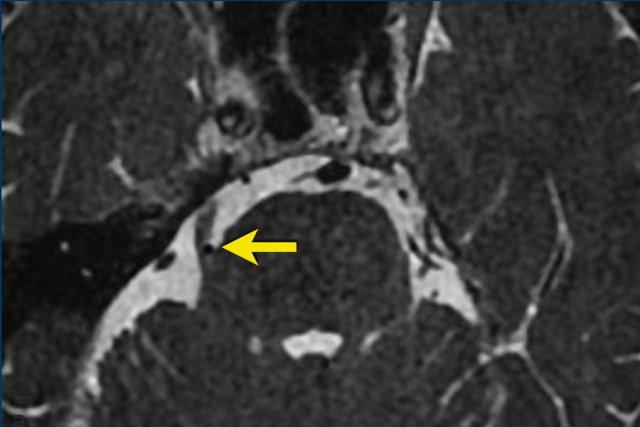

Các hình ảnh này thuộc về bệnh nhân nam 49 tuổi với biểu hiện rối loạn cảm giác nửa mặt trái và cảm giác tức nặng sau mắt trái.

Chuỗi xung T2W cắt ngang cho thấy một tổn thương tại hang Meckel và đoạn bể dịch não tủy của dây thần kinh sinh ba. Thành phần trong hang Meckel có cấu trúc đặc và ngấm thuốc tương phản từ đồng nhất trên ảnh T1W sau tiêm (mũi tên).

Thành phần trong bể góc cầu tiểu não gần như hoàn toàn dạng nang và chỉ ngấm thuốc ở vỏ nang.

Tổn thương được chẩn đoán là u schwannoma thần kinh sinh ba.

Sự phát triển của tổn thương dọc theo thần kinh, gây thắt hẹp tại lối vào hang Meckel, tạo nên hình ảnh kinh điển dạng “quả tạ” (dumbbell shape).